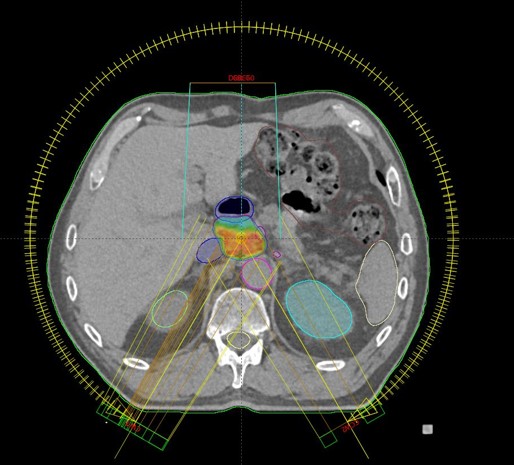

SBRT ppt recidivum locoregionalis tm oesophagei (30.09.2020. - 07.10.2020., TD 35 Gy/5 fr.)